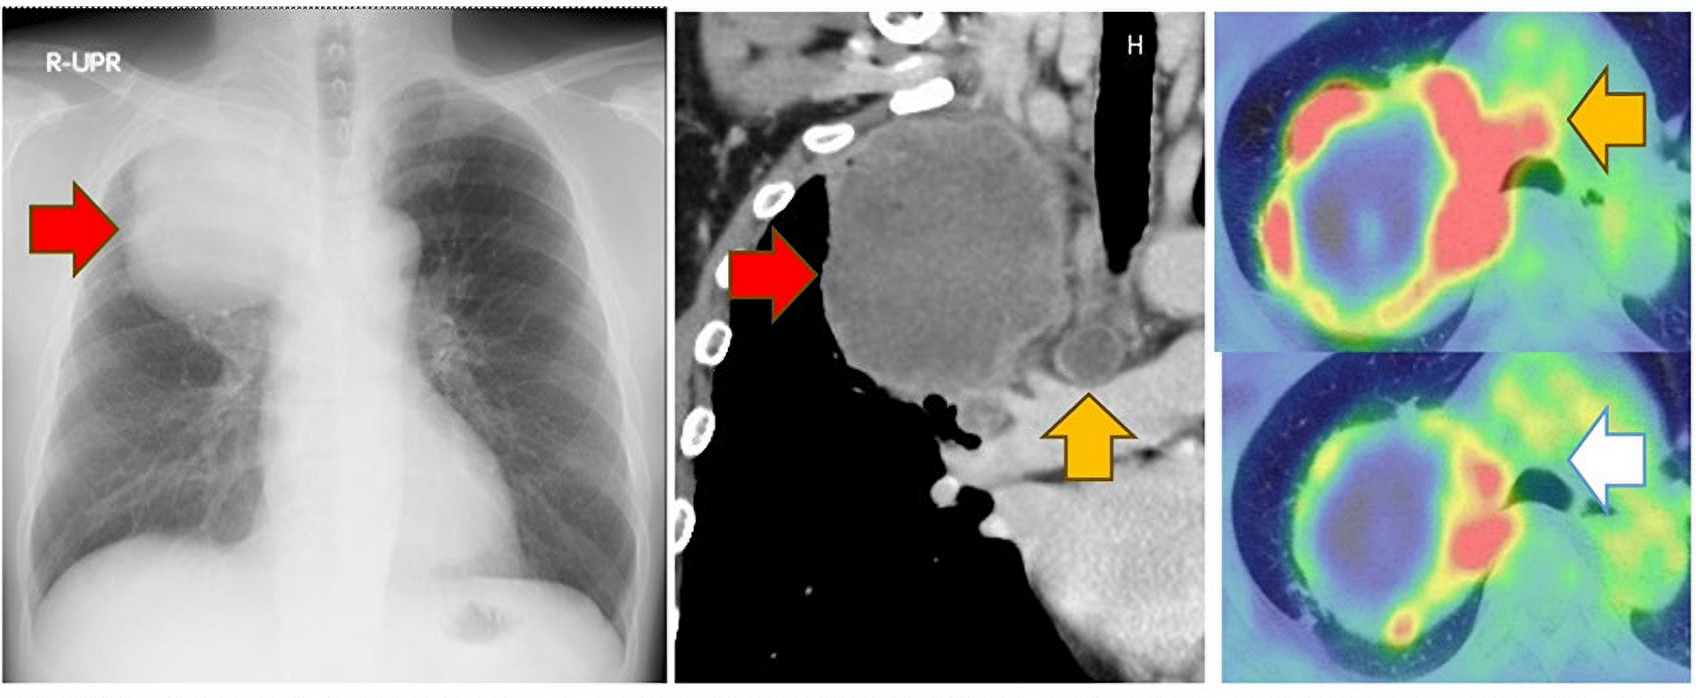

▲50代男性の患者さんです。最初に受診した段階で、12cm超の巨大な右上葉肺癌を認めました(※赤矢印)。 縦隔のリンパ節へ転移しており(※黄矢印)、ステージⅢB期と手術適応でなかったことから、化学療法を実施したところ、リンパ節への転移が消失(※白矢印)したため、根治を期待して手術を行いました。 術後3年以上経過して、再発なく過ごされています。